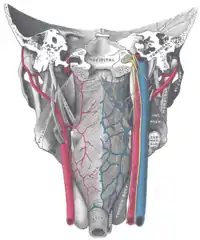

![]() Arterias del plano profundo del cuello. La arteria carótida interna nace de la arteria carótida común, señalada como Common caroti en el dibujo. | ||